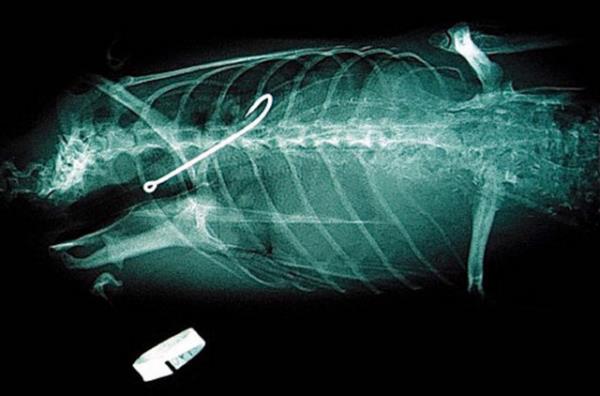

21. Hayvanat bahçesinde yaşayan bu Penguen'in midesinde ise yutmuş olduğu çengel görünüyor.

Hayvanat bahçesinde yaşayan bu Penguen'in midesinde ise yutmuş olduğu çengel görünüyor.